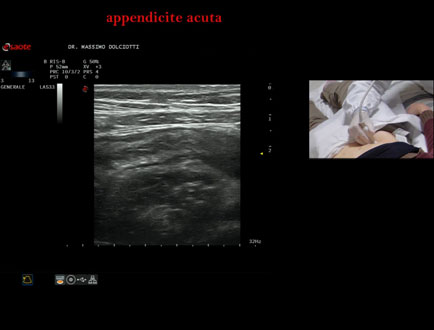

Commento all'esame: le immagini ed il video documentano, in sede ileo-cecale, appendice di spessore aumentato (11 mm - V.N. inferiore a 6 mm). Gli elementi ecografici segnalati orientano per appendicite acuta.

Conclusioni: appendicite acuta (acute appendicitis).

In collaborazione: Dr.ssa Marica Manfredi - Ancona, Dr. Ilir Qose - Ancona

Presentazione: Dr. Massimo Dolciotti - Ancona

Elaborazione digitale: Andrea Dini - Ancona